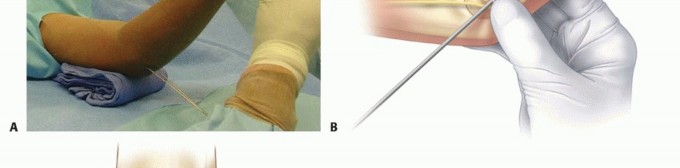

Percutaneous Leverage (Bernstein Technique)

Pesudo et al. and Bernstein et al. popularized the use of a percutaneous pin to manipulate the fracture fragments under fluoroscopy.

Anatomical Pitfall: During percutaneous reduction, the Kirschner wire must be introduced on the ulnar side of the radius. Introducing the wire laterally risks iatrogenic injury to the deep branch of the radial nerve (posterior interosseous nerve) as it traverses the arcade of Frohse.

Fig. 33-43 Radial neck fracture in relation to arcade of Frohse.